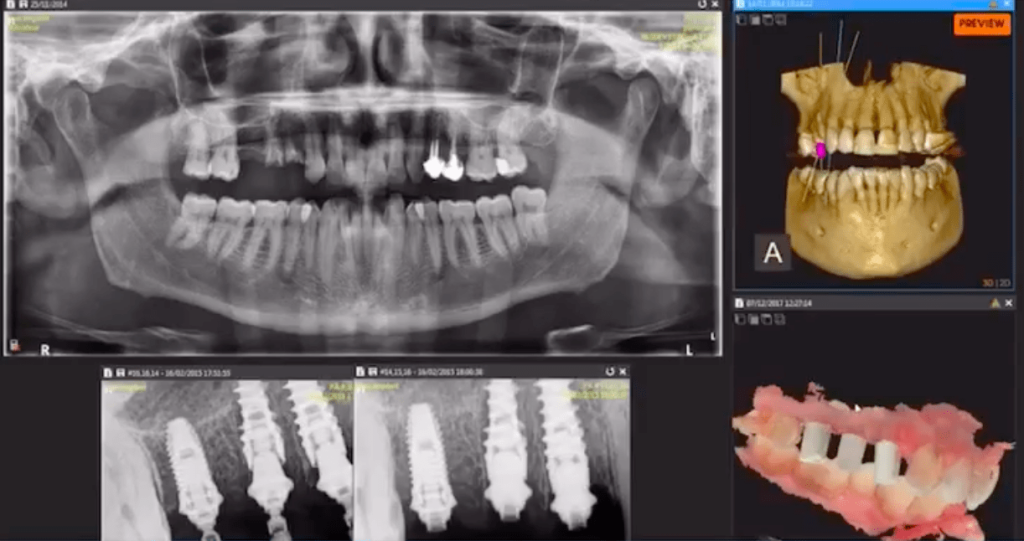

Точная диагностика с помощью 3D-рентгена перед началом лечения

Перед установкой импланта мы выполняем высококачественный 3D-рентген (RX 3D). Это исследование позволяет точно оценить ваш клинический случай, индивидуально спланировать лечение и подобрать наилучшее решение для достижения функционального и эстетичного результата.

Каждая полость рта уникальна, поэтому в Facialia мы уделяем особое внимание тщательному планированию ещё до начала процедуры. Это позволяет сделать лечение более безопасным, предсказуемым и полностью адаптированным к потребностям пациента.